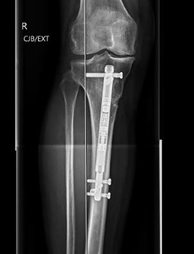

The technique, which involves inserting a nail – or rod – into the tibia and lengthening it externally with a magnet to relieve pressure on the damaged side of the knee, enables clinicians to treat the condition, delaying the need for partial or total replacements of the joint.

Using the new IM HTO technique, which incorporates the Nuvasive PRECICE OPTY-LINE System, clinicians insert a nail into the bone and slowly extend it using a magnetic connection via remote control to bend the bone into position until it is corrected through extension of the nail and creation of new bone.